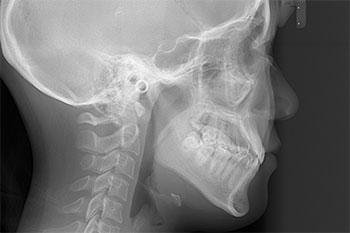

歯やあごの状態を正確に知るために、口や顔の写真、レントゲン写真(頭部X線規格写真、パノラマ等)、歯型などの資料を採ります。特に頭部X線規格写真(セファログラム)は、上下のあごの大きさやそのバランス、あごや唇の形態、歯の傾斜角度、口元のバランスなどの状態を正確に知ることができる検査です。